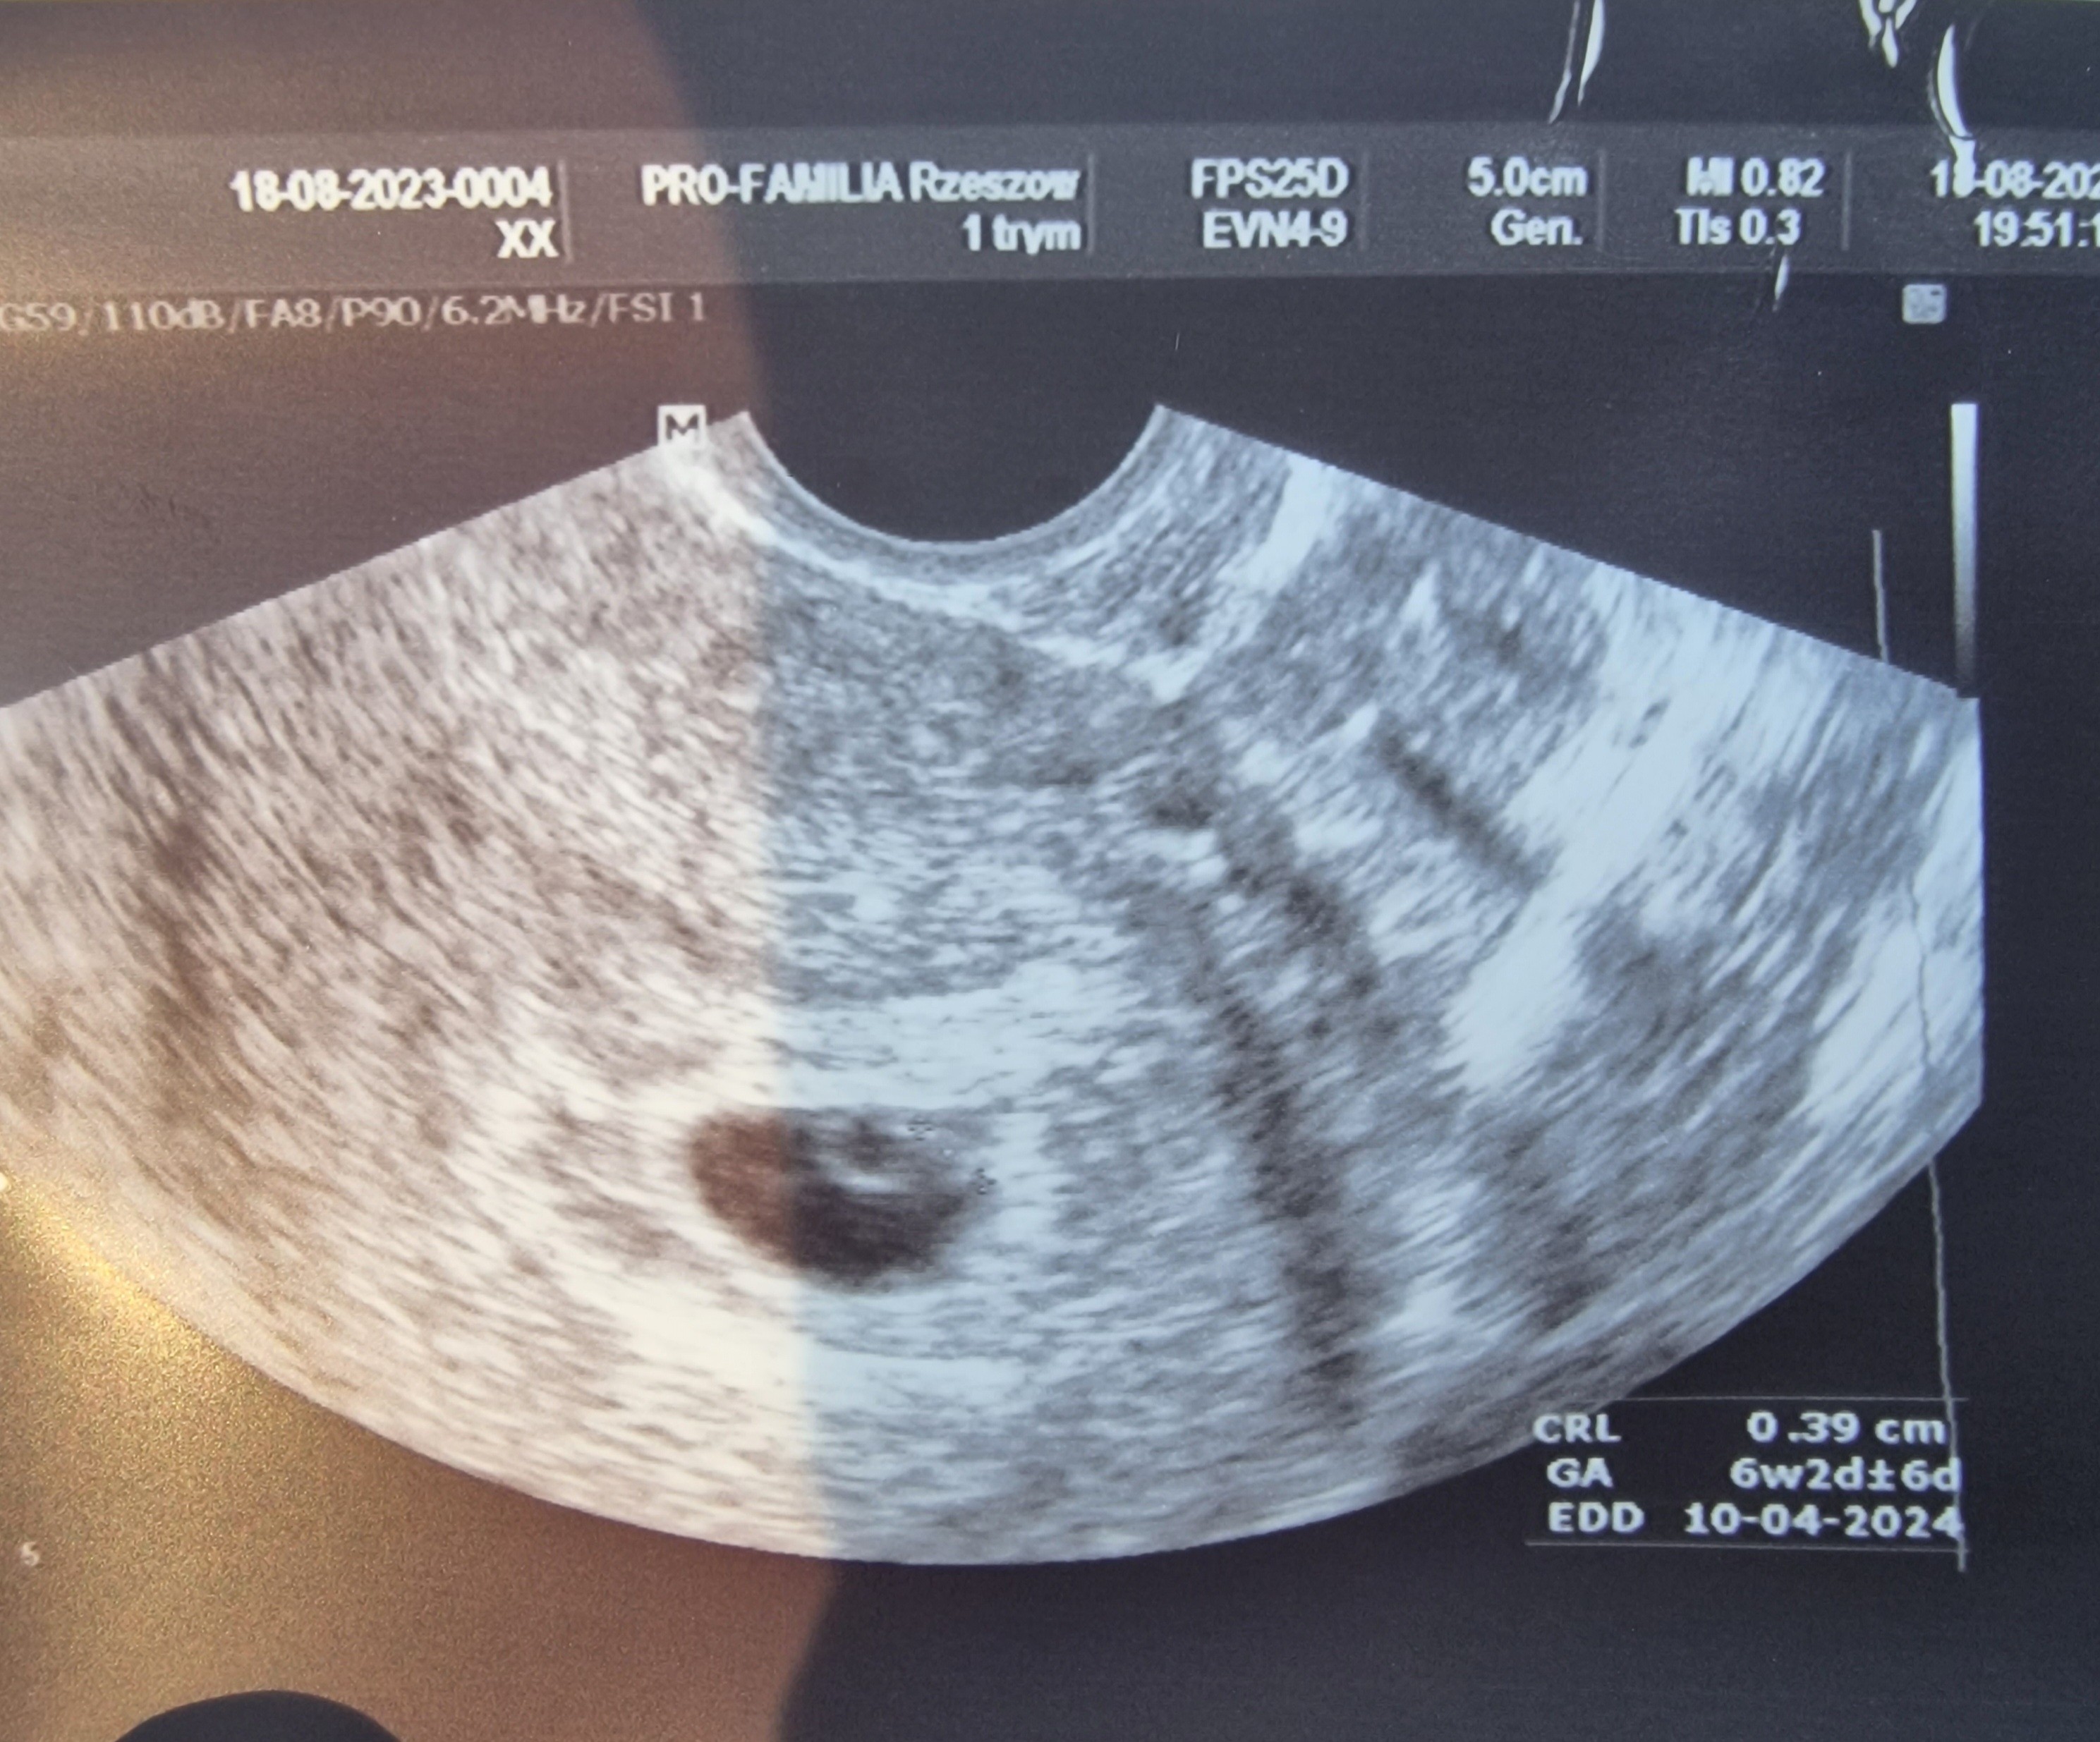

Oglądając to zdjęcie USG przypomniało. Mi się że mój pęcherzyk wyglądał całkiem Podobnie (ciąża 5 lat temu) i wszystko było ideolo

Tylko twoje usg jakby przybliżone

Załączniki

• Screenshot_2023-08-18-17-06-07-212_com.google.android.apps.photos.jpg

Screenshot_2023-08-18-17-06-07-212_com.google.android.apps.photos.jpg

208,3 KB · Wyświetleń: 98